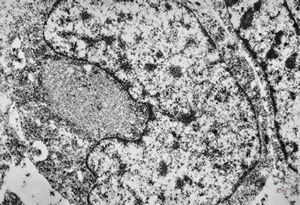

M, 11y. | mast cell

M, 13y. | mast cell